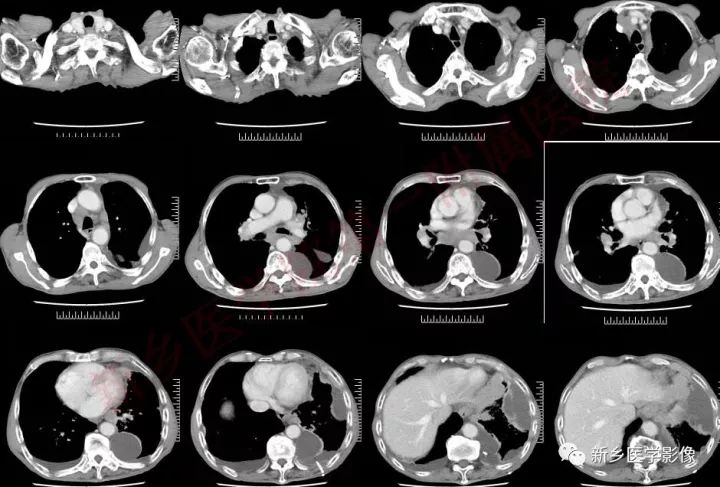

患者,男,73岁

主诉:间断胸痛、胸闷12天。

12天前劳累后出现左侧胸痛、为间断性钝痛,咳嗽及深呼吸时明显,无放射、能耐受。感胸闷、气短,活动后明显,休息后能缓解,无心慌、夜间阵发性呼吸困难、双下肢水肿等不适,稍有咳嗽、有少量白痰,无发热、畏寒、盗汗、乏力、食欲减退等不适,起始未在意,后上述症状逐渐加重,5天前于滑县人民医院检查胸部CT发现肺部阴影并左侧包裹性胸腔积液,给予左氧氟沙星输液治疗并行胸腔穿刺术2次,共抽取出胸水约1700ml,起始胸水为淡黄色,后为血性,期间于当地防疫站行PPD检查为阴性,因患者症状缓解不明显且肺部阴影及胸水性质未能明确,今为求进一步诊治来我院,门诊以“1、肺部阴影并左侧胸水 结核 占位2、营养不良”收入我院。患者自发病来,神志清楚,精神尚可,饮食可,睡眠可,大便正常,小便正常,体重减少4kg。

右颈部肿物病理结果回示:形态结合免疫组化,符合小细胞癌转移。

免疫组化结果显示:CD56( ),CgA( ),CK( ),Ki-67( 90%),Syn( ),LCA(-),S-100(-),Vimentin(-)。

肿块形态及强化:

中央型小细胞肺癌主要起源于5级以上支气管,分叶少,边界较光滑,不易发生空洞,肿块一般沿支气管长轴蔓延,包绕支气管,增强后呈中度强化;周围型小细胞肺癌,肿块多呈结节状或葡萄状,结节状病灶多为单结节型,形态较规整,边缘较光滑,无分叶或浅分叶,毛刺征及胸膜凹陷出现率低;葡萄状病灶表现为沿小支气管生长的串珠状大小不等结节病灶,密度较均匀,少有空泡征、空气支气管征,增强后,出现轻中度强化。这主要与小细胞肺癌的病理形态有关,小细胞肺癌,癌细胞小而呈短梭形,胞浆少,癌细胞排列密集,因此形成的肿块密度较大,瘤体密实,内聚力强,纤维成分少,血供相对丰富,肿块各方向生长的速度也较均衡,使得小细胞肺癌肿块不容易形成较深的分叶和空洞。

小细胞肺癌的沿支气管壁生长的特点,加上其肿块周围的淋巴结、淋巴管弥漫受侵的特性,使得小细胞肺癌周围肺间质广泛受侵,间质增厚,其中的血管壁受侵甚至管腔内受侵有癌栓形成,造成受侵血管呈“冰冻状”。中央型小细胞肺癌,肿块较大时肿块与肺门、纵膈的肿大淋巴结融合,包绕临近较大血管形成“冰冻纵膈”。CT表现为肺动脉主干或分支最常见。

胸腔积液与胸膜

小细胞肺癌沿淋巴管扩散的特点,容易造成小叶间隔线增厚、凸起,当侵及胸膜时,可引起胸膜多发结节影或磨玻璃影,伴有恶性胸腔积液。CT表现为胸膜面不规则增厚、凹凸不整的细小结节影及胸腔积液,增强可见增厚的胸膜及结节影轻至中度强化表现。按照美国退伍军人医院肺癌研究组分期系统标准,双侧胸腔积液发生时,病情已进展到广泛期,对于患者的治疗和预后将产生重要的影响